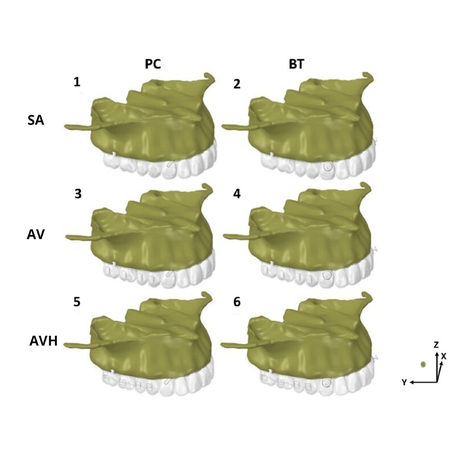

Objetivo: Este estudo investigou a influência de attachments nos dentes posteriores superiores usando alinhadores e ancoragem esquelética extra alveolar, combinada com precision cuts (PC) ou botões (BT) nos caninos superiores. Métodos: Modelos virtuais 3D foram criados a partir de uma tomografia de um paciente adulto jovem, caucasiano, com dentição permanente intacta desde os segundos molares e apresentando má oclusão de Classe II, divisão 1. Foram utilizados seis modelos de...

Objective: This study investigated the influence of attachments on the maxillary posterior teeth using aligners and extra alveolar skeletal anchorage applied to precision cuts (PC) or buttons (BT) on the upper canines. Methods: 3D virtual models were created from a tomography of a young adult Class II, division 1 Caucasian patient with healthy and non-restored full complement of permanent teeth (except third molars) was used. Six finite element models of the maxillary teeth with aligners and...